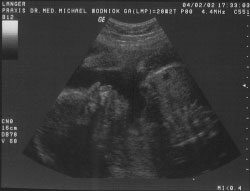

Diese beiden Fotos bekamen meine Eltern am 04.02.2002.

Jetzt wohne ich bereits 29 Wochen (8. Monat) im Bauch meiner Mama und ich muß sagen, mir geht es in meiner Wohnung noch immer richtig gut. Mama und Papa fühlen meine Tritte immer deutlicher und Mama beschwert sich schon manchmal bei meinem Papa, weil sie jetzt ständig auf die Toilette muß. Aber ich kann doch auch nichts dafür. Die Wohnung wird immer enger und ich kann mich kauf noch bewegen. Wenn das so weiter geht, muß ich wirklich darüber nachdenken, auszuziehen.